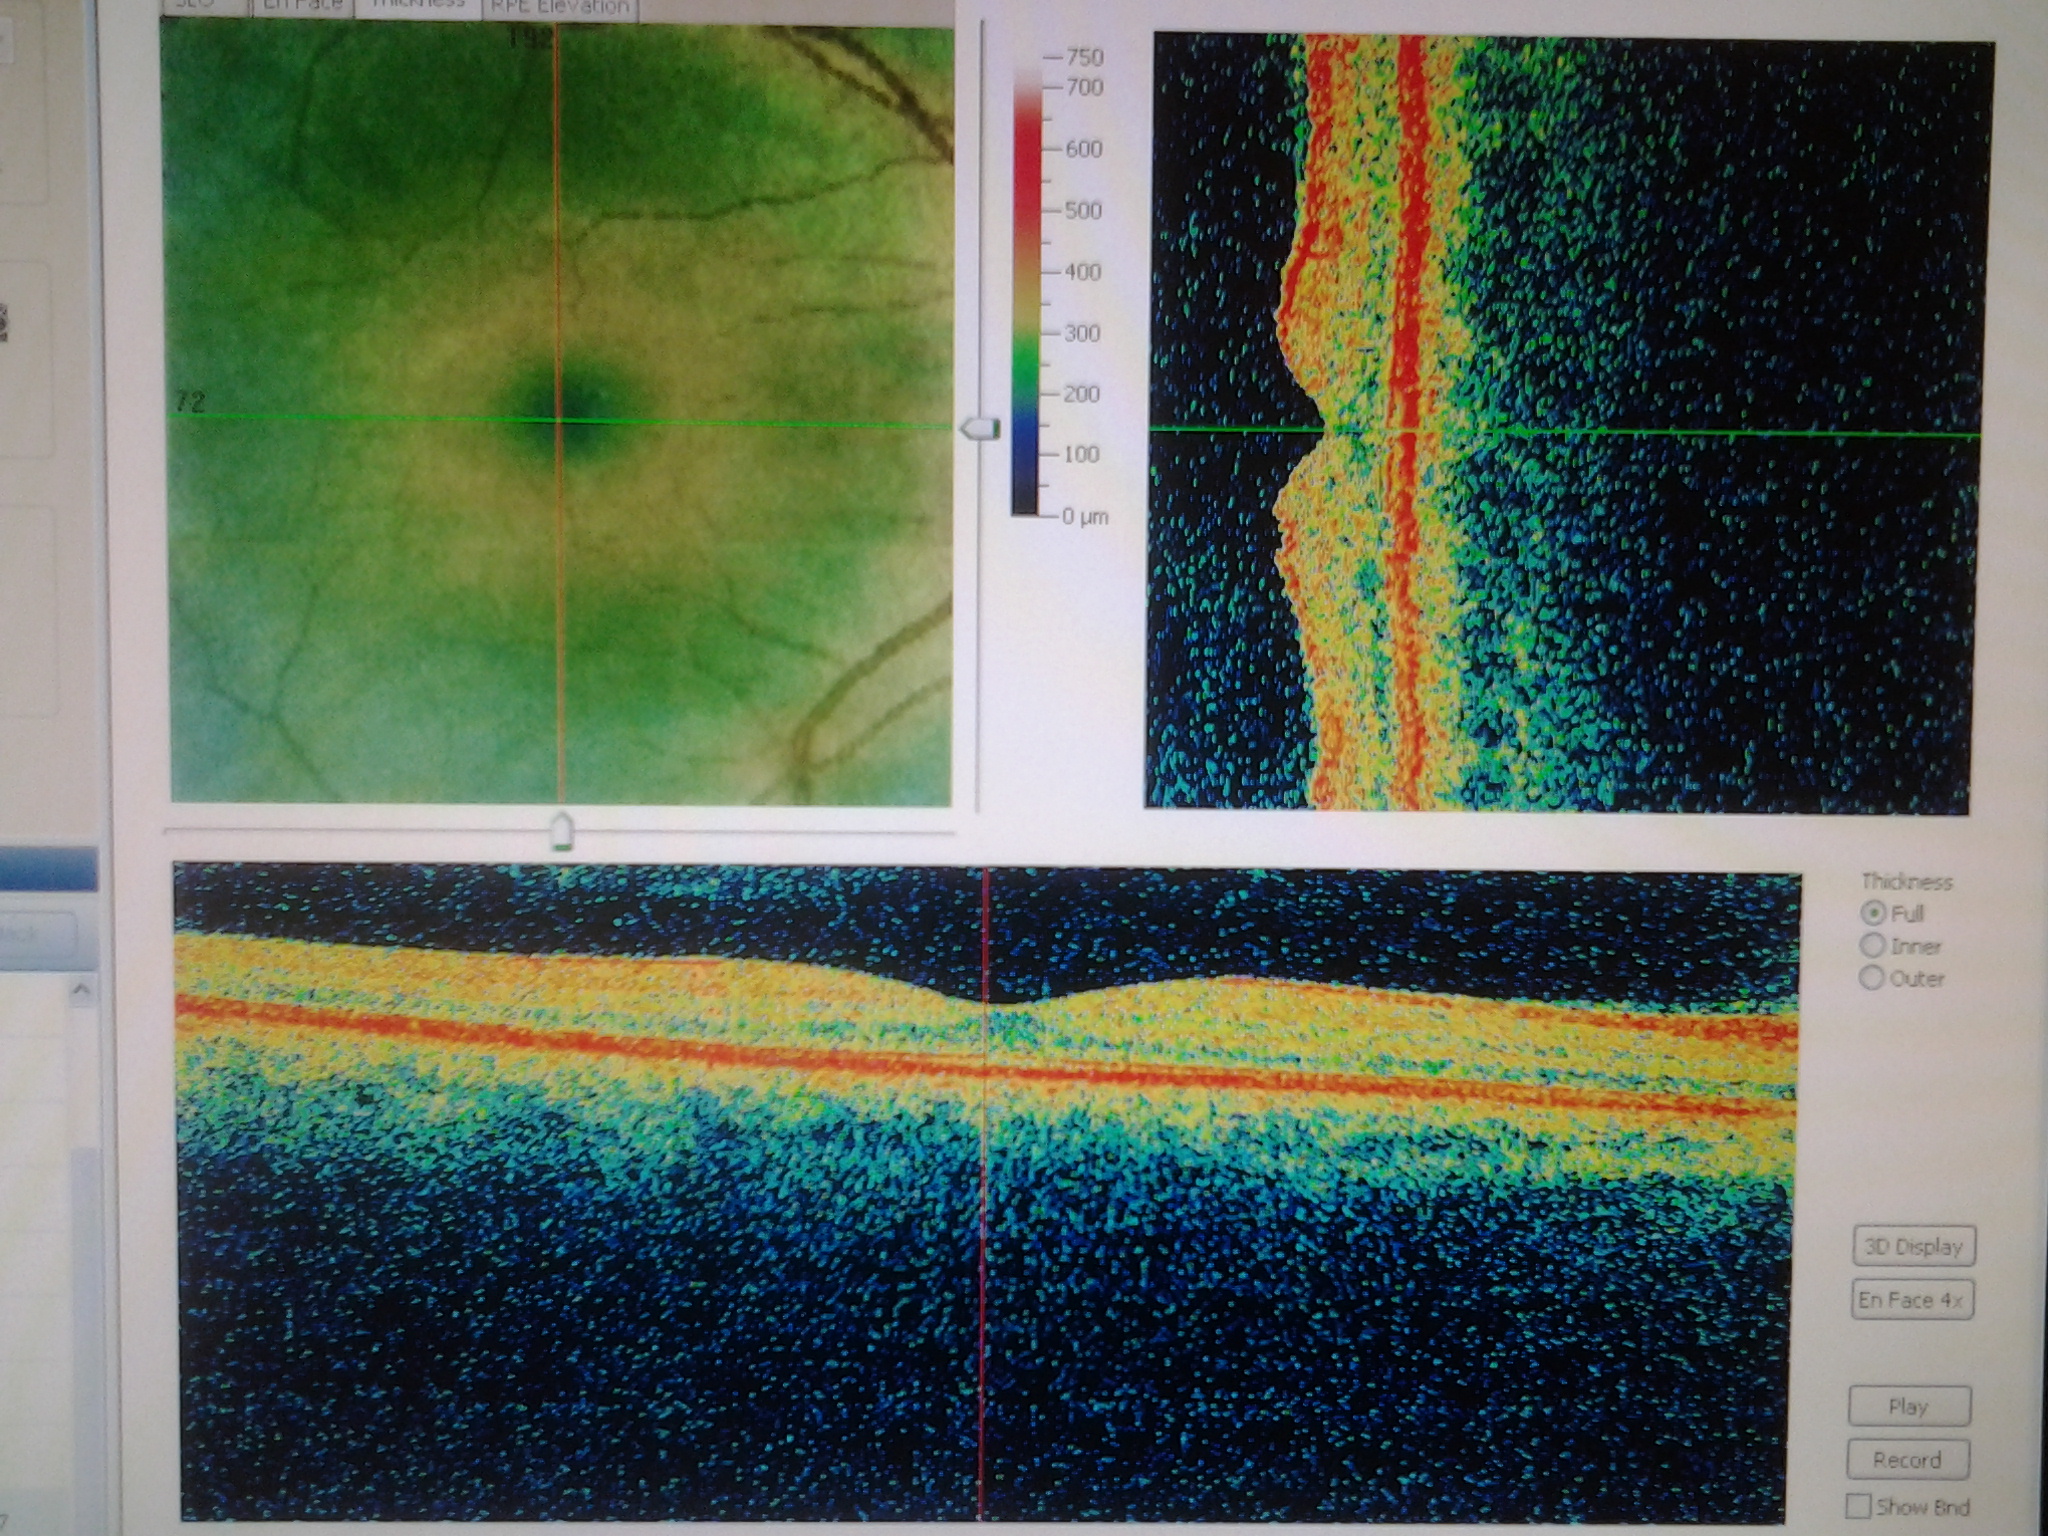

Диагностика зрения: Когерентная томография сетчатки